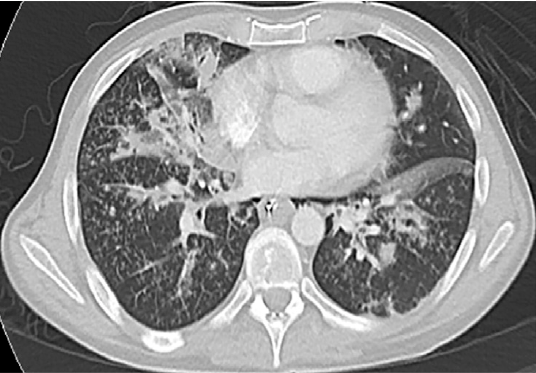

A 38-year-old male presented to the emergency department via ambulance with a 4-day history of worsening agitation, confusion, altered mental status, fever and cough. The patient's wife reported seeing a text on the patient’s phone about possible recent intravenous injection of buprenorphine with naloxone. Upon arrival to the ED, the patient was afebrile (37.5°C) but extremely agitated. Initial vitals were notable for marked hypoxia (SpO2 74%) and tachycardia (140 bpm) with stable blood pressure (146/74 mmHg). On physical exam, the patient appeared to be a young, uncooperative man with diaphoresis, increased work of breathing, and accessory muscle use. Track marks were noted on his bilateral upper extremities. Due to worsening respiratory failure and agitation, the patient was emergently intubated. A CT angiogram showed a distinct tree-in-bud pattern with findings of pulmonary hypertension (Figure 1). The patient received vancomycin, piperacillin/tazobactam, and was admitted to the intensive care unit.

Figure 1. Axial cuts of computed tomography (CT) scan of patient’s chest suggesting excipient lung disease. Dashed circles indicate centrilobular periarteriolar micronodules that create a tree-in-bud pattern. Solid arrows show centrilobular micronodules in the lungs corresponding to perivascular granulomas, also often seen in excipient lung disease.

The initial evaluation of a patient with a history concerning for ELD should include chest radiograph, continuous pulse oximetry and arterial blood gas analysis. The chest radiograph in ELD typically shows widespread, small (2-3 mm) well-defined micronodules, often occurring in the midlung zones.6 The typical CT findings include numerous centrilobular micronodules in the lungs (Figure 1: solid arrows), corresponding to perivascular granulomas. Although centrilobular nodules typically reflect bronchiolar disease, in the setting of excipient lung disease, they reflect embolic arteriolar disease.7 Centrilobular periarteriolar micronodules can also appear as a tree-in-bud pattern (Figure 1: dashed circles), further mimicking bronchiolar disease.7 The “tree-in-bud pattern” described in the case refers to small centrilobular nodules of soft tissue attenuation connected to multiple branching linear structures of similar caliber that originate from a single stalk. (See Table 1 for differential diagnosis of "tree-in-bud" pattern on CT imaging.)